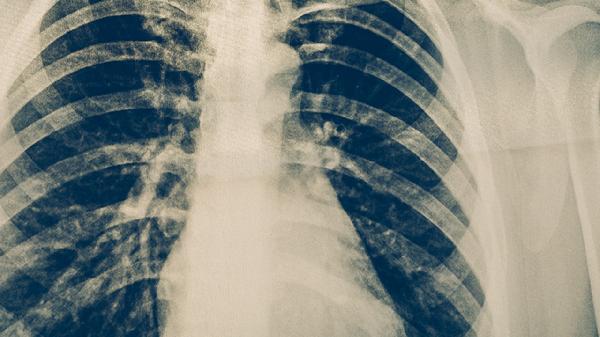

肺結(jié)核是由結(jié)核分枝桿菌引起的慢性傳染病,主要危害包括肺部組織損傷、全身多器官受累、傳染性風(fēng)險(xiǎn)及并發(fā)癥。肺結(jié)核可能導(dǎo)致肺功能下降、咯血、呼吸衰竭,還可能引發(fā)結(jié)核性腦膜炎、骨結(jié)核等肺外結(jié)核病,未經(jīng)規(guī)范治療可危及生命。

肺結(jié)核病灶會(huì)破壞肺泡和支氣管結(jié)構(gòu),形成空洞或纖維化病變,導(dǎo)致持續(xù)性咳嗽、胸痛和活動(dòng)后氣促。嚴(yán)重時(shí)可出現(xiàn)肺不張或毀損肺,長(zhǎng)期反復(fù)感染可能誘發(fā)慢性阻塞性肺疾病。治療需規(guī)范使用異煙肼片、利福平膠囊、吡嗪酰胺片等抗結(jié)核藥物,療程通常需6個(gè)月以上。

肺結(jié)核患者應(yīng)保證每日優(yōu)質(zhì)蛋白攝入量達(dá)1.2-1.5克/公斤體重,優(yōu)先選擇瘦肉、豆制品和乳清蛋白粉。康復(fù)期可進(jìn)行八段錦、呼吸操等低強(qiáng)度運(yùn)動(dòng),避免劇烈活動(dòng)加重缺氧。居住環(huán)境保持50%-60%濕度有利于呼吸道防護(hù),每3個(gè)月需復(fù)查胸部CT直至病灶穩(wěn)定。密切接觸者應(yīng)做結(jié)核菌素試驗(yàn)篩查,新生兒須接種卡介苗預(yù)防重癥結(jié)核。